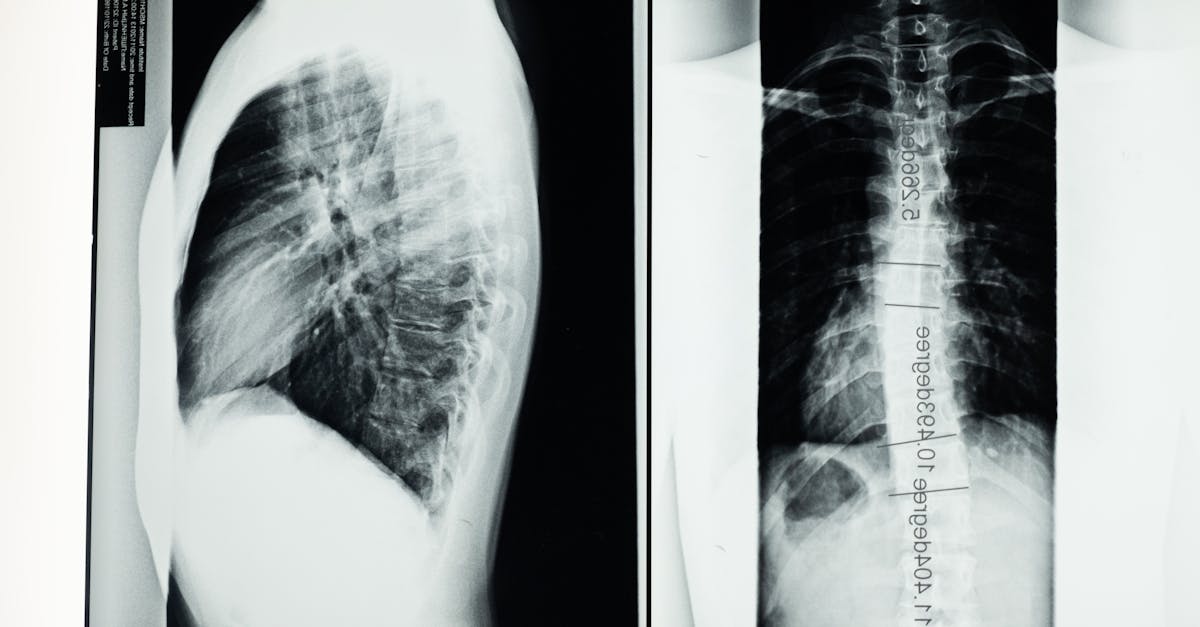

Les étapes essentielles pour diagnostiquer une protrusion discale complexe avant un programme intensif de décompression neurovertébrale